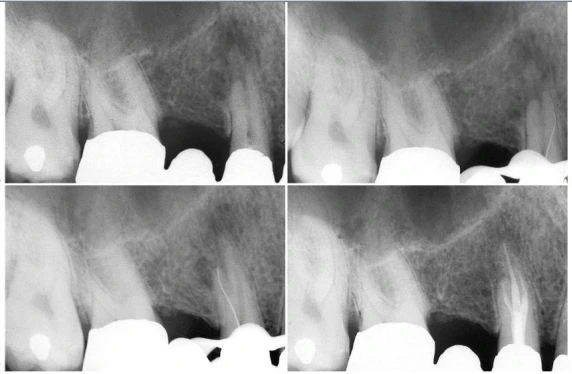

Hình 8.21. A.Phim sau điều trị của răng cửa bên hàm trên bên trái. Hình dạng và góc đọ của thấu quang, đường viền rõ và với kích cỡ của một nang. B. Sưng ở vùng khẩu cái. C. Hình ảnh mô học của tổn thương (×2,5). D. Phóng đại lớn, tổn thương mang những đặc trưng của u hạt (×250). E. Phim sau điều trị. Việc trám ngược được thực hiện ở răng cửa giữa bên phải. F. Một năm sau. Lưu ý rằng “sẹo quanh chóp” lớn vài mm phía trên chân răng cửa bên.

Hình 8.27. Phim Xquang trước điều trị của răng của bên hàm trên bên phải cho thấy hình ảnh tổn thương dạng nang lớn. Răng nanh và răng cối nhỏ đáp ứng dương tính với test thử tủy sống, trong khi đó răng cửa giữa cho kết quả âm tính. B. Một áp xe cấp tính lớn ở vùng xương ổ răng đã phát triển do một tổn thương mạn tính và nó thấy được ở vùng khẩu cái. C. Phim sau điều trị. D. Tám năm sau phẫu thuật cắt chóp. Do các triệu chứng sưng cấp tính tái diễn (có lẽ liên quan đến việc trám bít vùng chóp không đủ do gặp khó khăn khi làm khô ống tủy), cắt chóp và trám ngược bằng amalgam được thực hiện ở răng cửa giữa và răng cửa bên.